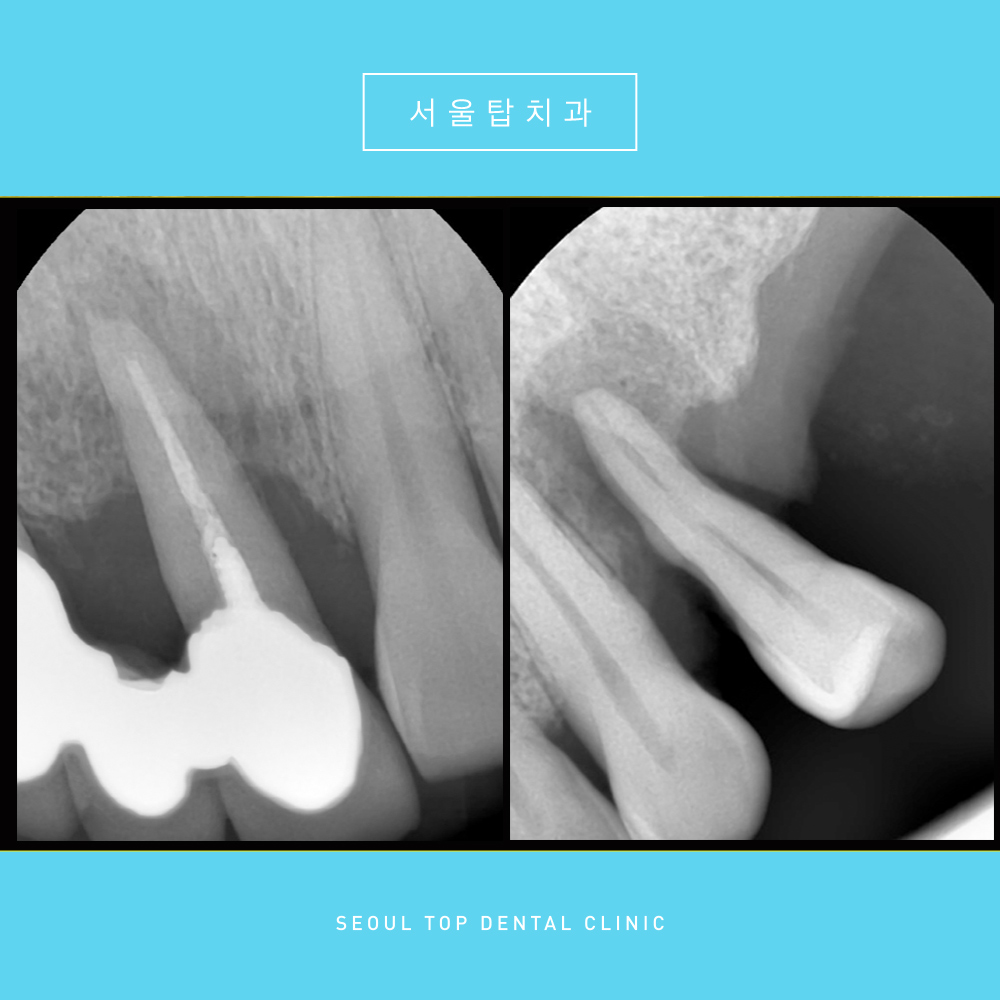

조금 더 자세한 사진을 촬영해

노란색 표시의 치아들을 확인해보았습니다.

건강한 치아나 뼈가 있는 부분은

밀도가 높아 방사선이 투과하지 못해

하얗게 나온 것에 반면,

좋지 않은 부위는 어둡게 나타나는데요.

위의 사진을 보시면

치아나 잇몸뼈 주변으로

검게 보이는 부분을 확인하실 수 있습니다.

뼈가 굉장히 많이 녹아 있는 상태였고

치아를 잡아주는 잇몸뼈가 없으니

흔들림도 심한 상황이였답니다.

해당 치아들은 더 이상 살리지 못하여

발치가 필요한 상황이었습니다.